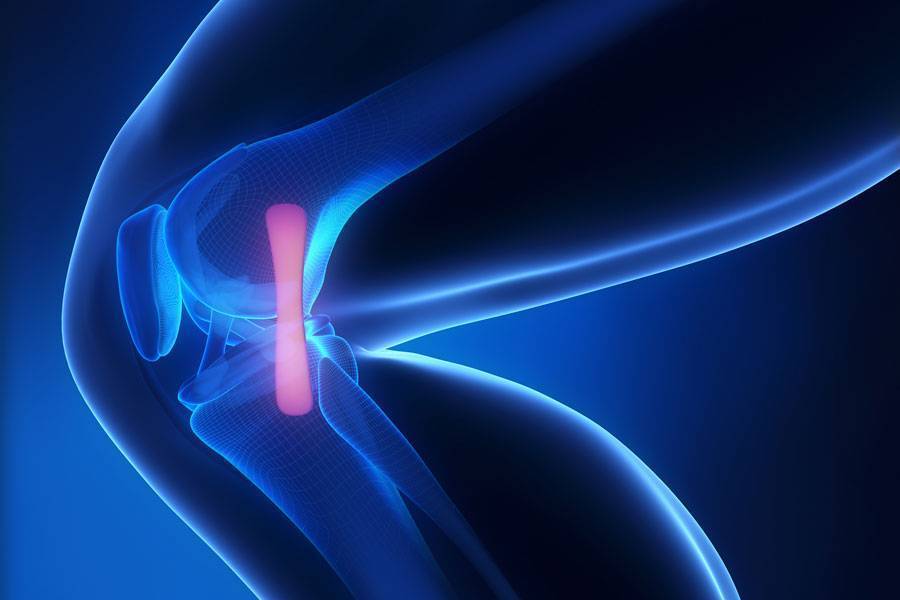

Die Orthopädie ist ein medizinisches Fachgebiet, das sich mit der Prävention, Diagnose und Behandlung von Erkrankungen und Verletzungen des Bewegungsapparates beschäftigt. Knochen, Gelenke, Muskeln, Sehnen und Bänder müssen gemeinsam funktionieren, um uns Beweglichkeit und Stabilität zu ermöglichen.

Auf unserer Seite finden Sie umfangreiche Informationen zu orthopädischen Beschwerden und Erkrankungen. Von der Arthrose über Bandscheibenvorfälle bis hin zu Kreuzbandriss und weiteren Sportverletzungen: wir geben Ihnen einen Überblick über die häufigsten orthopädischen Krankheitsbilder, wie sie behandelt werden können und inwieweit ein Bildgebungsverfahren, wie eine (z.B. MRT Knie, Rücken MRT) bei der Diagnose bei der Diagnose unterstützend wirken können.

Unsere Liste zu den häufigsten orthopädischen Problemen ist alphabetisch von A-Z geordnet. So finden Sie schnell und unkompliziert den Beitrag, der Ihnen weiterhilft. Von Krankheiten, über Verletzungen bis hin zu schmerzhaften Zuständen wie Arthrose, Meniskusschaden und Schleimbeutelentzündung – hier finden Sie die wichtigsten Informationen.